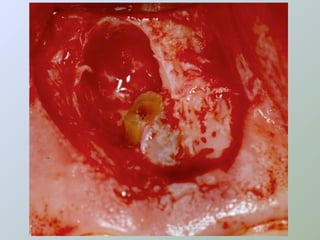

Acesso ao periápice

• Freqüentemente o

osso cortical sobre o

ápice é reabsorvido

expondo uma lesão de

tecido mole

• Ampliar a abertura óssea

• Cinzel

• Broca esférica cirúrgica

• Expor a raiz e boa parte da

lesão

CURETAGEM

O tecido inflamatório em torno do

ápice radicular deve ser removido

para:

• Ganhar acesso e melhorar a

visibilidade

• Obter material para histopatológico

• Reduzir a hemorragia